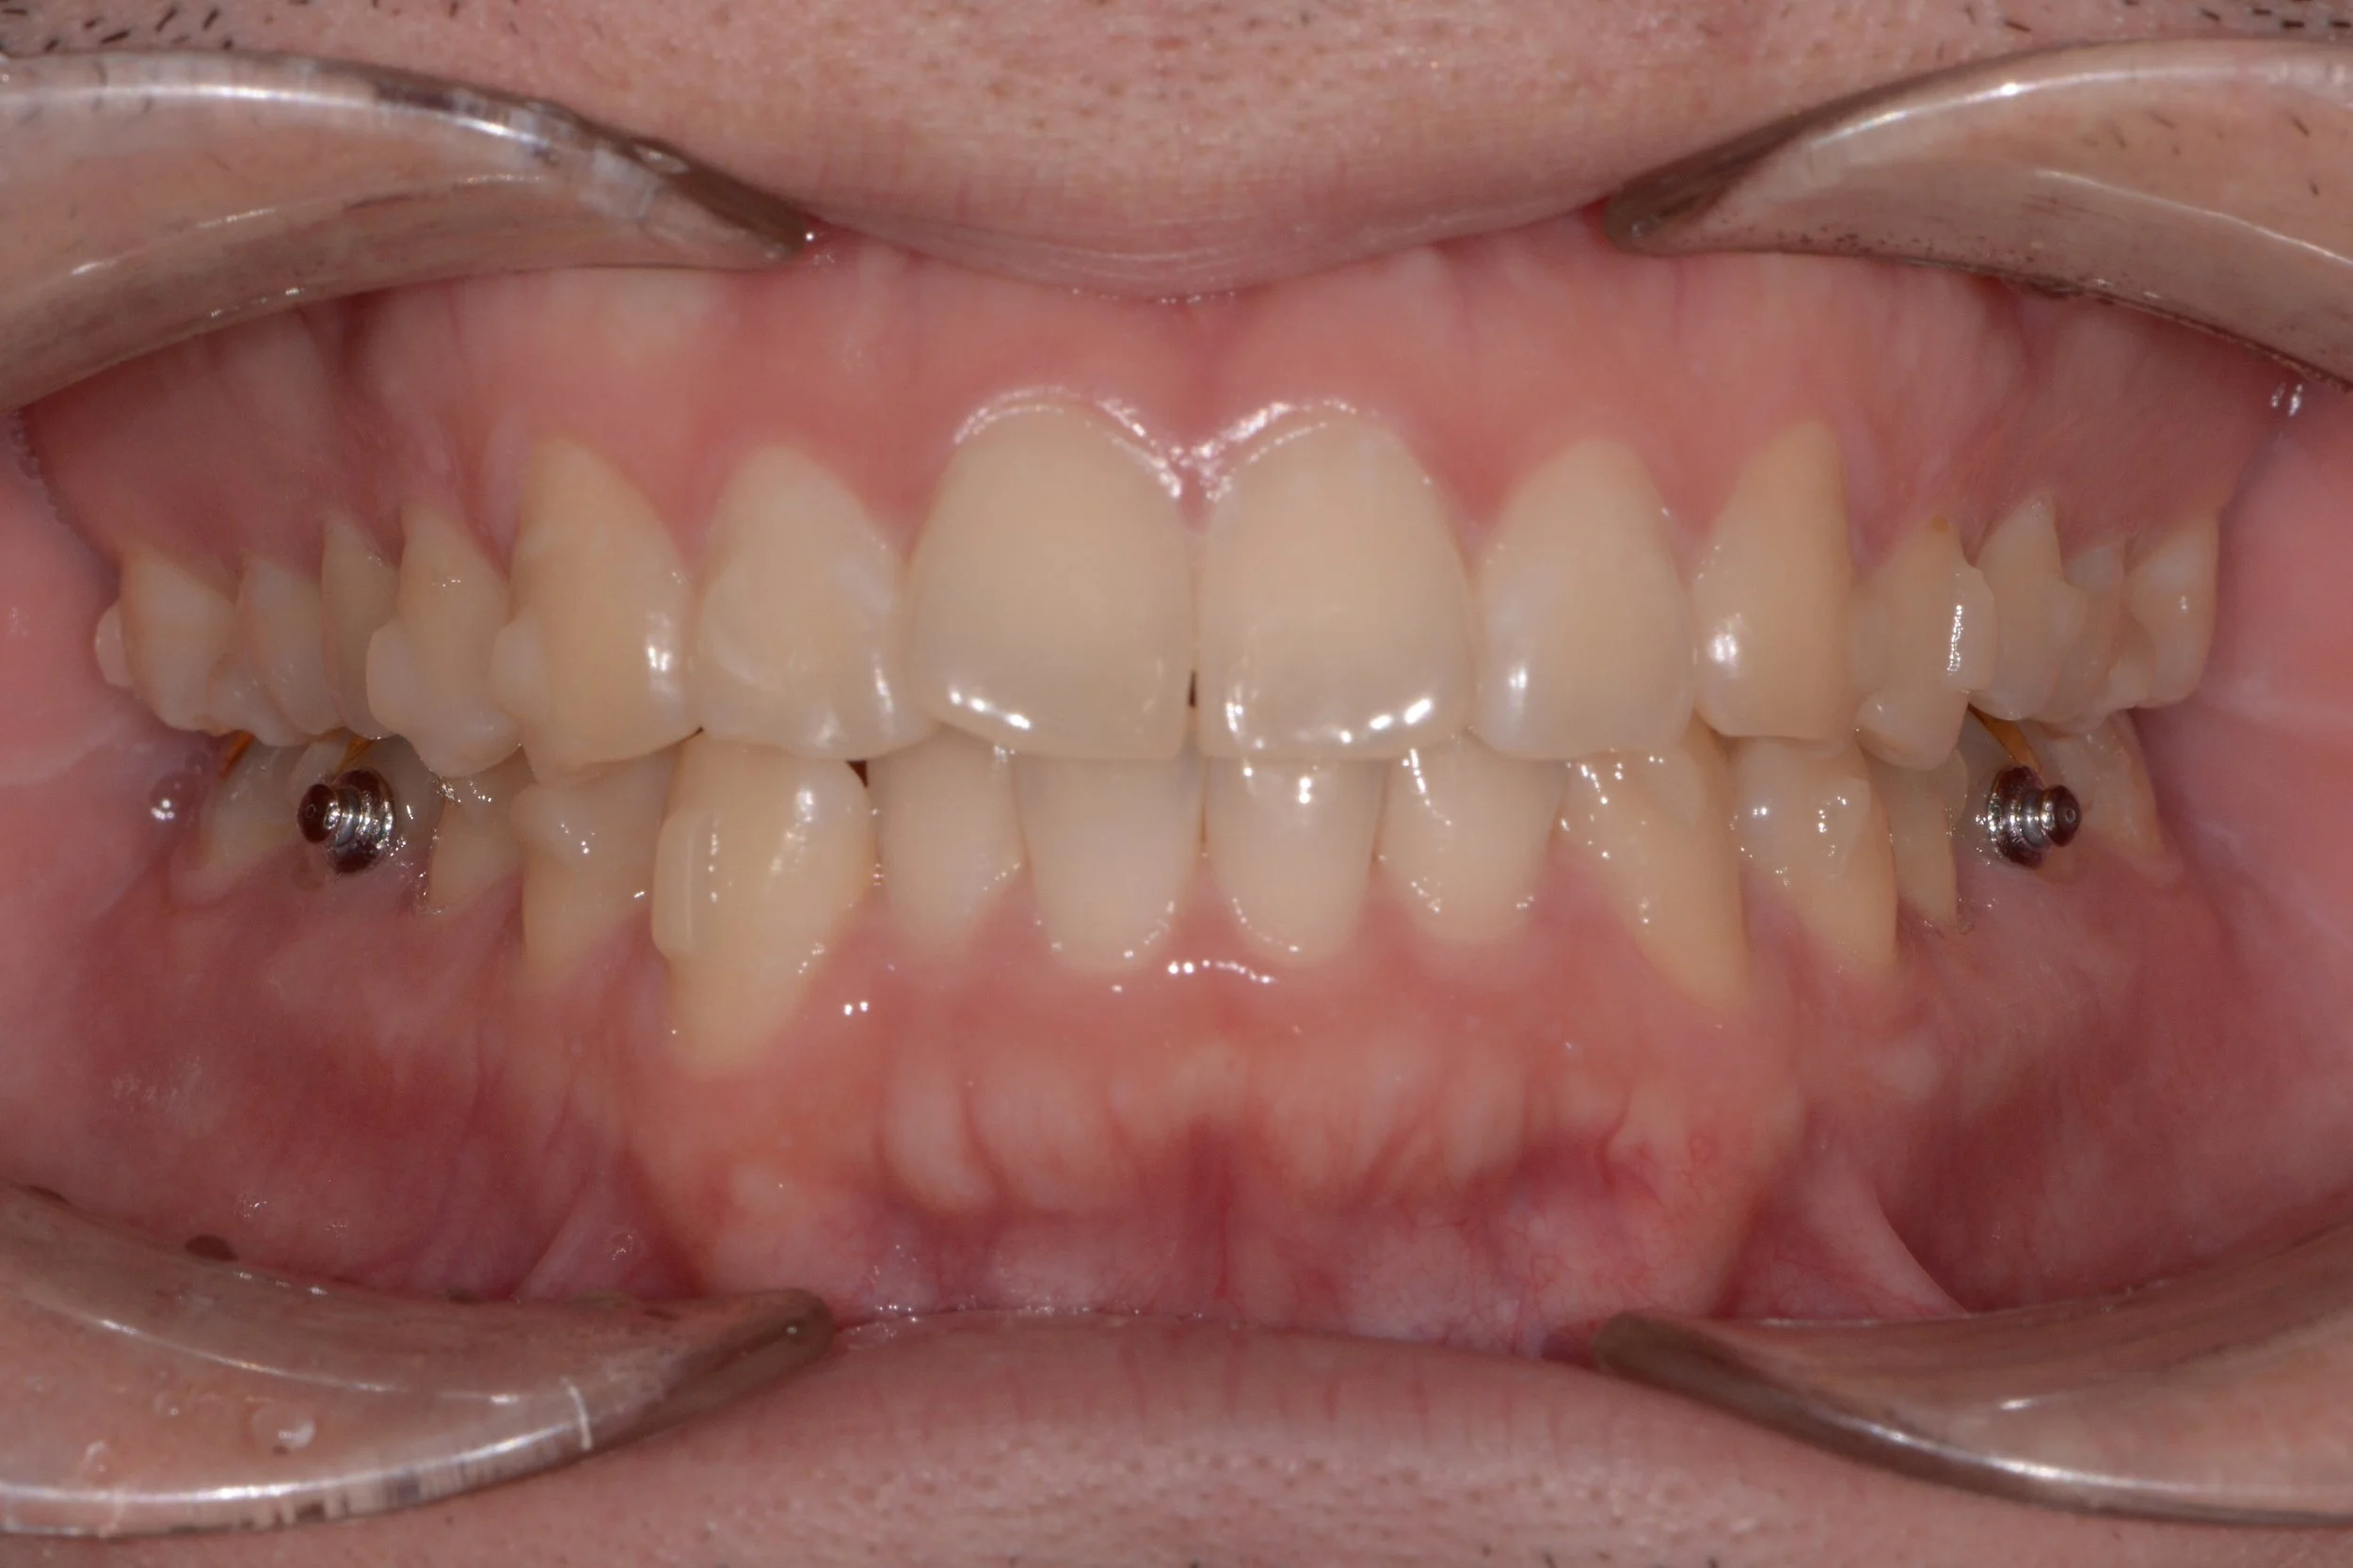

투명 교정 치료 1년 경과 후